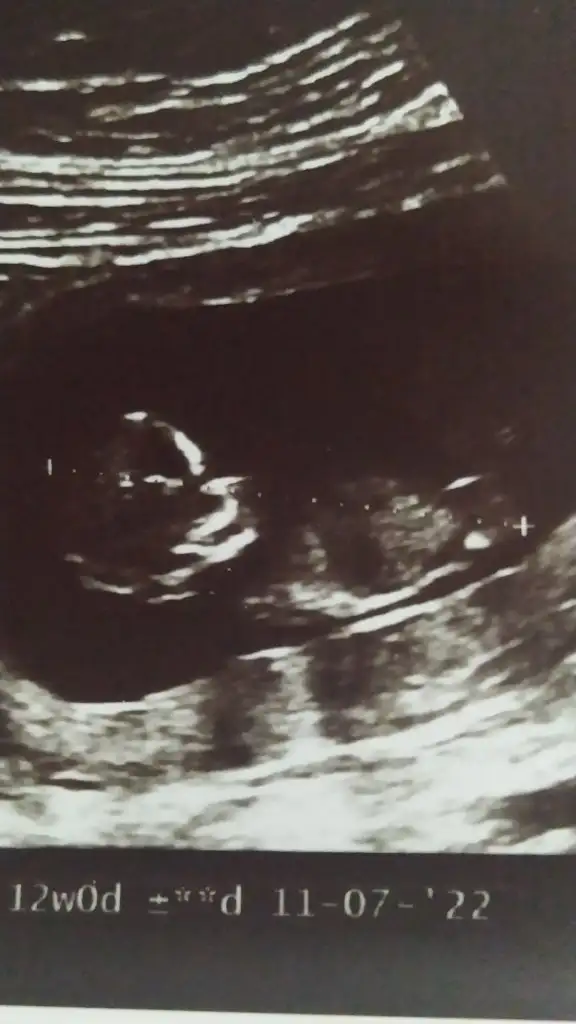

Ikra meyra canım 12+0 yorum yapabilirmisin acaba ?

Eklentiler

• IMG_20211227_173514.webp

19,8 KB · Görüntüleme: 83